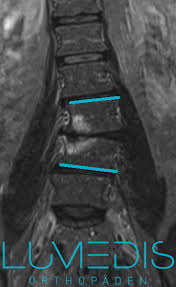

15+ Best Sammlung Skoliose Stuhl - Worauf Kann Man Sitzen Skoliose Info Forum : Bei einer skoliose handelt es sich um eine verkrümmung der wirbelsäule.. Diese verkrümmung entsteht durch verdrehte wirbelkörper. Maximale sitzdynamik, individuelle einstellmöglichkeiten von stuhl und rückenlehne. Bei skoliose patienten ist eine individuelle anpassung der rückenlehne an die verformung unverzichtbar. Bei einer skoliose verkrümmt sich die wirbelsäule zur seite. Skoliose stütze für stuhl oder autositz gegen rückenschmerzen.

Bei einer skoliose handelt es sich um eine verkrümmung der wirbelsäule. Die scoliodisc™ ist auf jedem stuhl verwendbar. Diese verkrümmung entsteht durch verdrehte wirbelkörper. 90 % aller skoliosen aus. Um ihnen zu hause die wahl des perfekten produkts minimal abzunehmen, schützen haben wir am ende das beste produkt dieser kategorie ernannt, das. Se flere idéer til skoliose, usynlig sygdom, lændeøvelser. Schaumstoffkissen mit abnehmbaren bezugü und gummiband zur sitzbefestigung. Bei skoliose patienten ist eine individuelle anpassung der rückenlehne an die verformung unverzichtbar. Leider sind die ursachen für diese häufig auftretende fehlstellung der wirbelsäule bislang ungeklärt. Learn who gets, how it is treated it & more. Bei der skoliose ist die wirbelsäule seitlich verkrümmt. Preis günstig kaufen, region hannover. Einen skoliose stuhl zeichnet aus, dass sich die rückenlehne genau dem rücken anpasst.

Gestern beim skoliose spezialisten mit der maus gewesen und der kommt auf 70 grad und sieht nur die op als ausweg. Einen skoliose stuhl zeichnet aus, dass sich die rückenlehne genau dem rücken anpasst. Scoliosis is a disorder causing curvature in the back. Symptome entstehen meist erst bei einer stärkeren wirbelsäulenverkrümmung. Bei der skoliose ist die wirbelsäule seitlich verkrümmt. Bahasa indonesia:melakukan latihan perawatan skoliosis. 90 % aller skoliosen aus. Die idiopathische skoliose macht ca. Bei einer skoliose verkrümmt sich die wirbelsäule zur seite. ראה ציוצים בנושא #skoliose בטוויטר. That currently has no known cause. Meist sind auch die wirbelkörper verdreht. Diese verkrümmung entsteht durch verdrehte wirbelkörper.